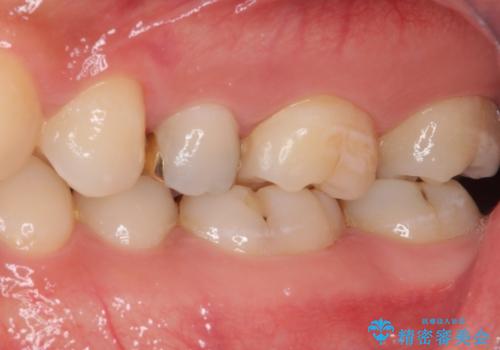

左上奥と右下奥に治療中の歯があり、虫歯を取っている途中で仮詰めの材料が充填されている状態でした。

仮詰め材を外すと虫歯が残っていたので、全てを取り除いた後に、ゴールドインレーの型どりを行いました。

ゴールドインレーをご自身で選択いただいたものの、どういった仕上がりとなるか不安を感じていたようですが、実際に装着された口腔内をご覧になり、思ったほど金属色が気にならないとのことでした。

咬んだ感触はご自分の歯のときと比べ全く遜色なく、患者様には大変満足していただきました。